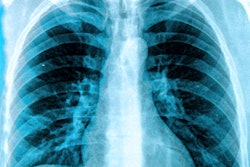

An artificial intelligence (AI) algorithm can accurately identify pneumothorax on chest x-rays by comparing new cases with a database of patients who have similar images and known findings, according to research being presented this week at the Vector Institute's Evolution of Deep Learning Symposium in Toronto.

A team of researchers from the University of Waterloo in Canada developed an AI model that analyzes chest x-rays of new patients by comparing the images with a database of over 500,000 chest x-rays with known diagnoses, including 30,000 exams with pneumothorax. The algorithm was able to identify 75% of the pneumothorax cases, an improvement over an average of less than 50% traditionally diagnosed on chest x-rays, according to the researchers.